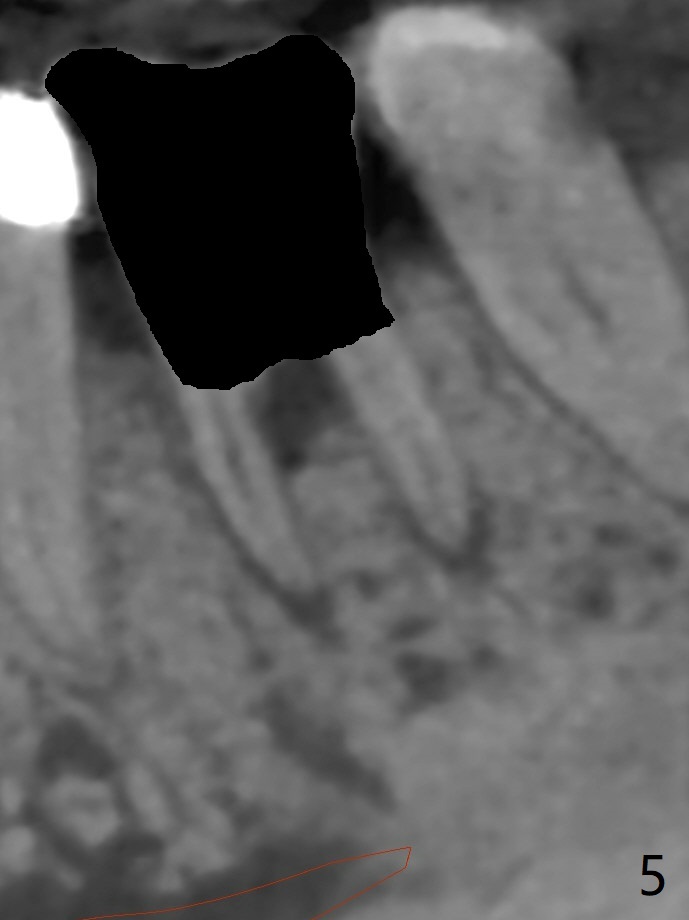

A 65-year-old man has nocturnal pain associated with #30 lingual furca caries and gingival recession (Fig.1,2). PRF (x2) and sticky bone will be used to repair the lingual soft and hard tissue defects. CT shows the submandibular fossa (Fig.3 <), dictating a short implant 10 mm, Fig.4). To place the implant in the septum (Fig.3 S), the coronal portion of the tooth is removed (Fig.5 black area) so that the roots are able to keep the osteotomy without deviation (Fig.6 red arrow). It is possible to place the implant in a trajectory mesiodistally (Fig.7 in fact after root extraction (arrows)). To prevent buccolingual deviation, a small implant (4 mm in diameter) is designed so that it will NOT touch the buccal (B in Fig.8) or lingual (L) plates. The bone density of the cortex and medulla is 2000 and 1400 units, respectively. To reduce the chance of implant fracture because of the narrow diameter in function, an implant with Titanium V will be used.